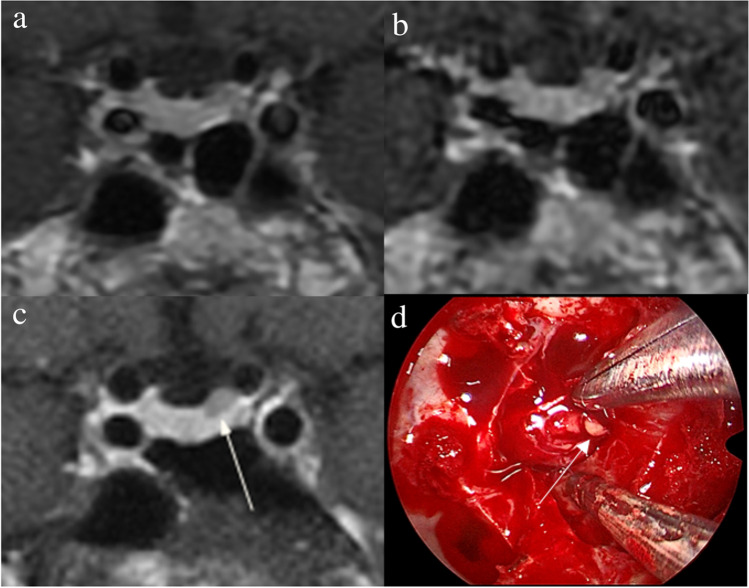

Figure 2 shows that a 5-mm pituitary microadenoma was identified on preoperative pituitary MRI. The margin of the lesion was fully delineated on hrMRI, but not on cMRI and dMRI. Figure 3 shows that a 3-mm pituitary microadenoma was missed on cMRI, but identified on dMRI and hrMRI. Figure 4 shows that a 5-mm pituitary microadenoma was correctly diagnosed on hrMRI, but missed on cMRI or dMRI. Figure 5 shows that a 4-mm pituitary microadenoma was evident on coronal images as well as reconstructed axial and reconstructed sagittal images on hrMRI.

Fig. 4.

Images in a 43-year-old man with Cushing’s disease. The lesion is missed on (a) coronal contrast-enhanced T1-weighted image and (b) coronal dynamic contrast-enhanced T1-weighted image obtained with two-dimensional (2D) fast spin echo (FSE) sequence. c Coronal contrast-enhanced T1-weighted image on high-resolution MRI obtained with 3D FSE sequence shows a round pituitary microadenoma (arrow) measuring approximately 5 mm with delayed enhancement on the left side of the pituitary gland. d Intraoperative endoscopic photograph for microsurgical resection of the 5-mm pituitary microadenoma (arrow)